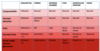

Refractive Errors

- SHape and size has impact on refraction of light but axial length has greater effect

- Hypermetropia/ myopia - due to difference in axial length then image may be formed behind or in front of retina not retinal plane lik emmetropria.

Astigmatism

- Cornea is not spherical

- Different radii of curvature in different axes

- In this case the verticsl radius is hsorter than horizontal radius so the curvature of the cornea is steeper in the vertical axis than horixontal axis

- To correct this a cyclindrical lens is needed with different powers in different axis

- Often described as rugby ball eyes